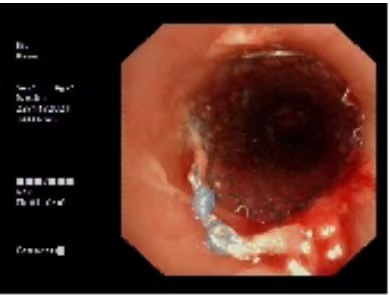

气管镜下主支气管仅见一缝隙